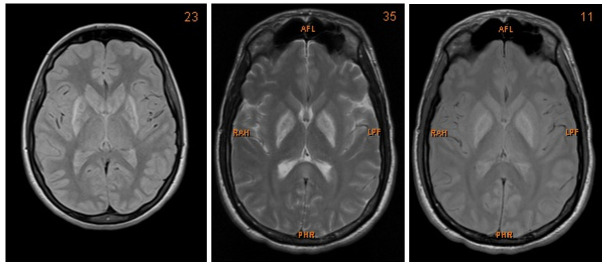

We present a case of a 27-year-old Caucasian man who was admitted to the Intensive Care Unit (ICU) after multi-intoxication. Drug screening on admission identified the following substances: opiates, benzodiazepines, cannabinoids, crack cocaine, methadone and amphetamine. Due to the history of drug abuse he was unemployed. During the first days the patient was in coma, with Glasgow Coma Scale of 5 points. After slow amelioration of his status he presented with severe dysarthria, dysphagia, as well as bilateral parkinsonism and dystonia of his extremities. The neurological examination showed a bilateral positive Babinski sign, global rigidity in all extremities as well as symmetrical hyperreflexia. Furthermore, he suffered from high fever that resolved after treatment with benzodiazepines. Therefore, vegetative symptoms accompanying the patient on admission were interpreted as drug withdrawal syndrome. Both, CT and MRI showed bilateral hypoxemic infarction of the basal ganglia and boundary zone ( Figure 1). Those changes could be the consequence of the mixed intoxication or could be attributed to only one harmful substance, especially crack cocaine or amphetamine. During the hospitalization he developed a tracheobronchitis and respiratory insufficiency due to acute respiratory distress syndrome (ARDS). Moreover, because of severe dysphagia he was nourished via percutaneous endoscopic gastrostomy. Further consequences of his primary condition included post ischemic epilepsy treated with levetiracetam (1000mg). After six months of intensive care, the patient was discharged from the hospital.